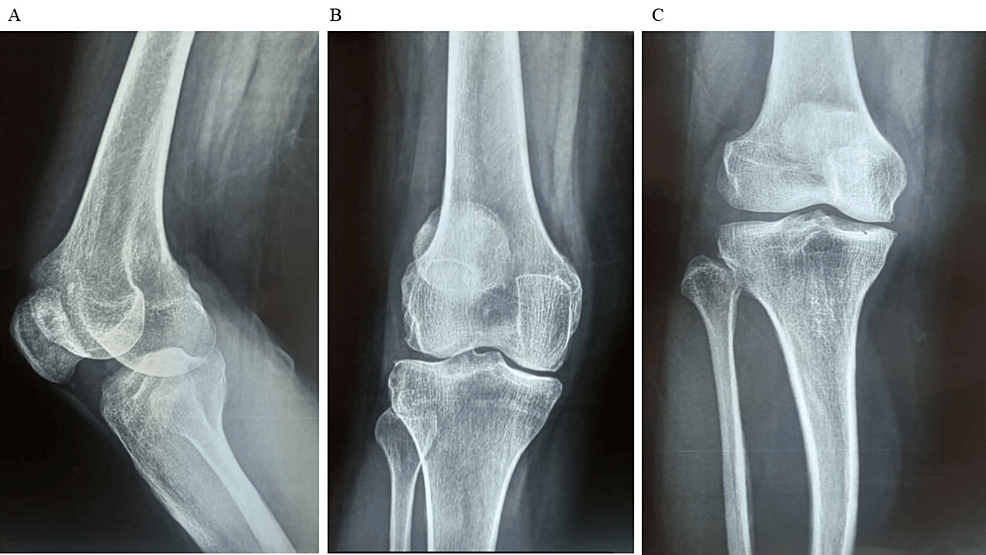

除了骨关节炎外,15名参与者还被发现患有骨缺损,占该队列的30%。这些缺损包括各种情况,例如骨折、退行性骨病或先天性畸形,突显了研究中涉及的骨科问题多种多样。下图1显示了开始干细胞治疗之前的骨骼侧视图和前后视图。